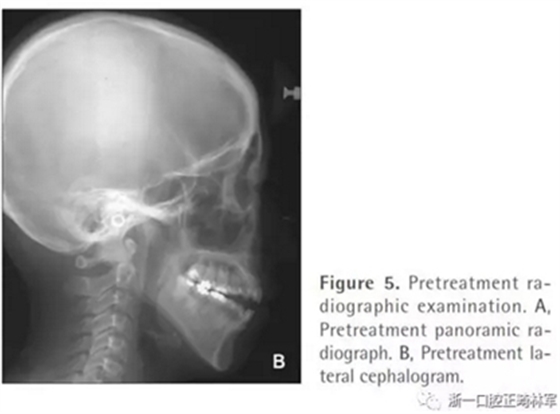

全景片顯示四顆智齒都存在,上頜切牙有牙根吸收,并且在雙側(cè)髁突都有相當(dāng)大的吸收(Figures 1B and 5A)。頭測分析顯示:ANB angle, 4.5°; FMA, 46.7°; U1-SN, 95.8°; L1-MP, 83.7°(Table 1, Figure 5B)。